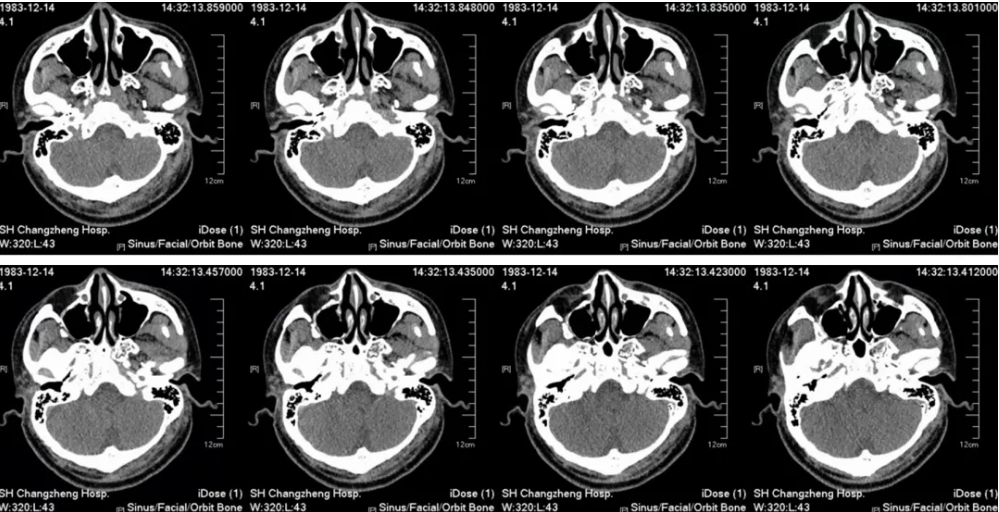

胸部CT(2025-9-18):双肺多发炎症,纵隔内及双侧腋窝见多发稍大淋巴结影,心隔角肿大淋巴结,双侧胸腔少量积液(图见后)。

胸部CT(2025-9-18)